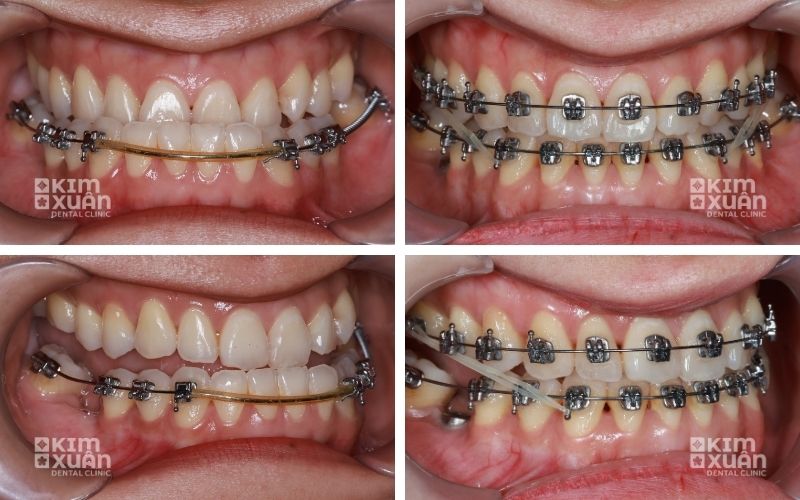

4.2. Phương pháp niềng răng móm

Niềng răng móm bằng mắc cài kim loại: Hiệu quả cao, chi phí tiết kiệm

Niềng răng móm bằng mắc cài sứ: Thẩm mỹ hơn, giá cao hơn mắc cài kim loại

Niềng răng móm bằng khay trong suốt Invisalign: Gần như vô hình, tháo lắp linh hoạt, chi phí cao nhất

Thời gian niềng răng móm thường kéo dài 18 - 30 tháng, tùy thuộc vào tình trạng răng, mức độ khớp cắn ngược và sự hợp tác của người niềng. Thời gian càng dài, chi phí điều trị có thể càng cao.